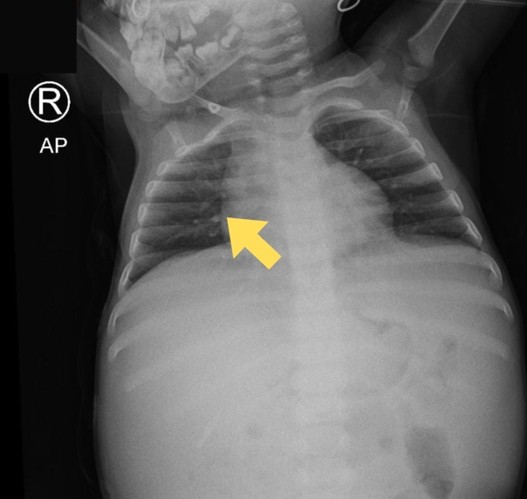

Her vital signs were within normal limits, but the anthropometric assessment indicated undernourishment (MUAC 76%). The abdominal examination showed distention (60 cm) with distant bowel sounds. The ascites drainage inserted at the previous hospital was well-placed, aiding in the removal of excess fluid. The tuberculin skin test showed an 8 mm induration, and the chest radiograph from the previous hospital showed hilar right lymphadenopathy (Figure 4). The MTB/RIF Ultra from gastric lavage was negative.